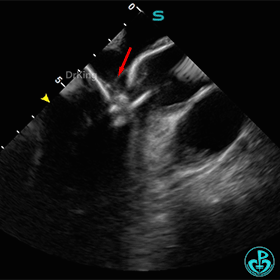

ICE下多切面观察封堵器形态及瓣膜活动状况

封堵器骑跨于室间隔两侧,周围瓣膜正常摆动。